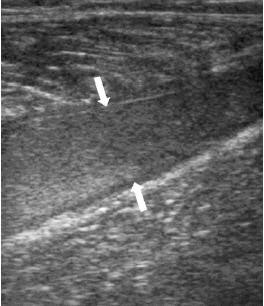

![]() |

A 35-year-old male with a partial rupture of the medial head of the gastrocnemius at the musculotendinous junction. Top, the longitudinal US image shows the medial head of the gastrocnemius muscle with partial discontinuity of the muscle fibers (double arrows). A small hypoechoic fluid collection (single arrow) is noted. G = gastrocnemius muscle, S = soleus muscle. Below, the longitudinal US image one week later shows a hyperechoic fluid collection (arrows). This fluid can be considered as most likely representing flesh blood.